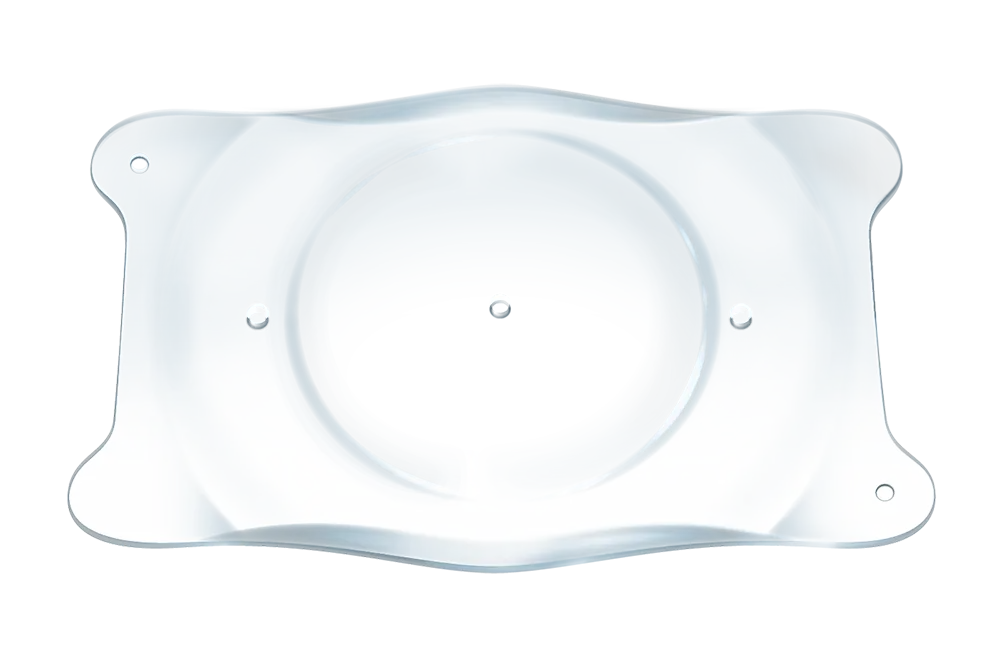

- EVO ICL is een phake lens.

- EVO wordt direct achter de iris en vóór de natuurlijke kristallijne lens geplaatst.

- De toevoeging van de centrale aqua port bij EVO vergemakkelijkt de stroom van aqueous humor doorheen de lens.

- De EVO-lens is een reversibel implantaat.